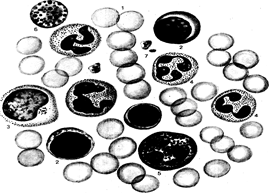

Рис. Клетки периферической крови человека.

1 – эритроциты, 2- лимфоциты, 3- моноциты, 4 – нейтрофильные гранулоциты, 5 – эозинофильные гранулоциты, 6 – базофильные гранулоциты, 7 – тромбоциты.